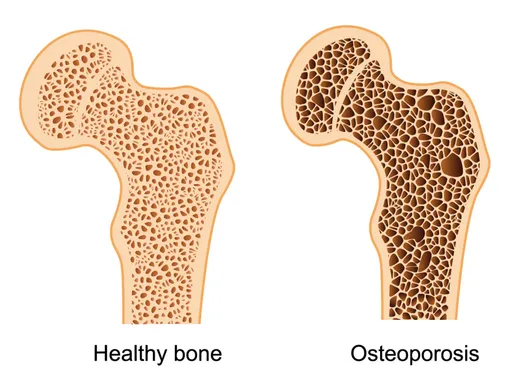

Osteoporosis